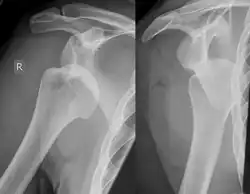

Ombro deslocado em raio-X.

Lesão de Hill-Sachs, ou Fratura Hill-Sachs, é uma depressão cortical na cabeça do úmero posterolateral. É o resultado de impactação forte da cabeça umeral luxada contra a glenóide anterior quando o úmero é luxado anteriormente.

A lesão está associada exclusivamente com a luxação glenoumeral anterior.[2] Quando o úmero é impulsionado à partir da cavidade glenoumeral, este impacta a cabeça, relativamente macia contra a borda anterior da glenóide. O resultado é um torrão, sulco ou achatamento no aspecto posterolateral da cabeça do úmero, geralmente oposto ao processo coracóide. O mecanismo que leva à luxação do ombro é geralmente traumático, mas pode variar, especialmente se houver história de deslocamentos anteriores. Esportes, quedas, convulsões, brigas ou virar na cama podem ser causas de deslocamento anterior.